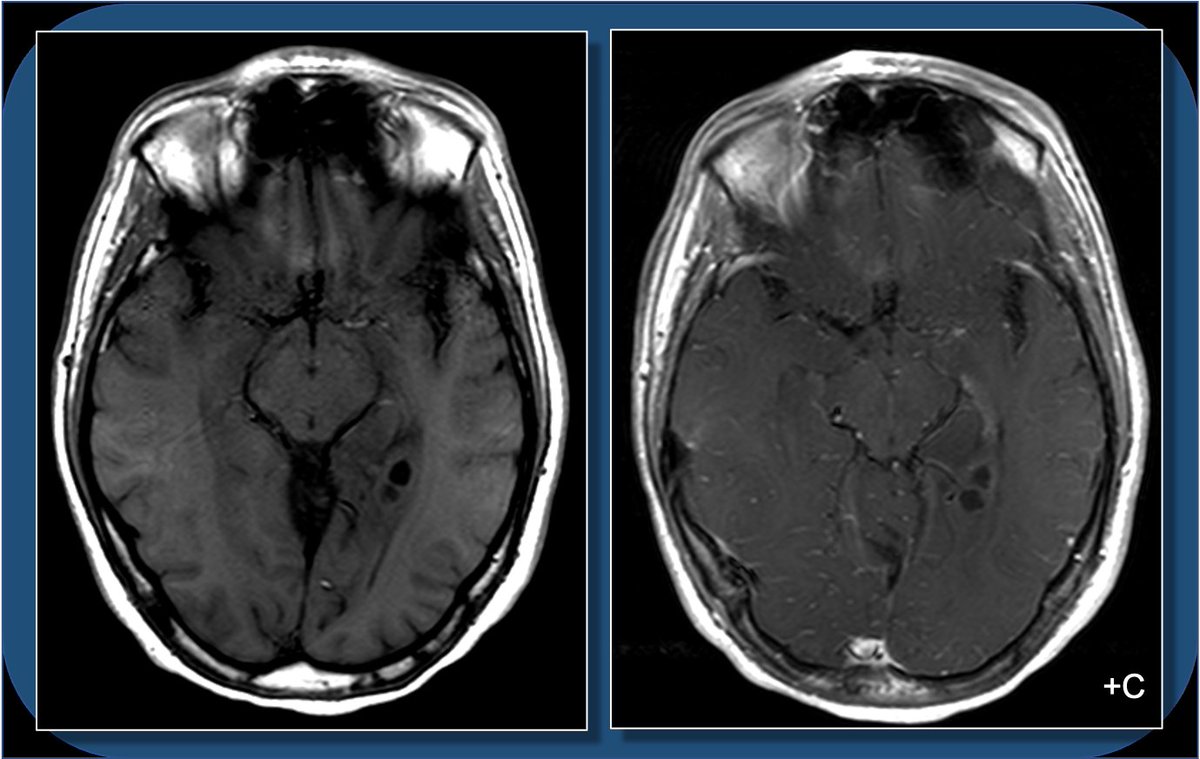

Hey #radres and #MEDstudents - a #neurorad case for you today. 18yoF w/ seizure. What do you see? What is the ddx? And WHERE is the lesion? Case explanation and gyral #neuroanatomy explanation coming soon.

18yoF with seizures. The FLAIR images show focal cortical expansion with cystic components, suggesting a cortically based tumor.

T1 images show mild T1 hypointense mass with cystic components, and minimal if any enhancement. So what’s the differential for a cortically based tumor in a child or young adult who presents with seizure? Pathology following resection c/w ganglioglioma.